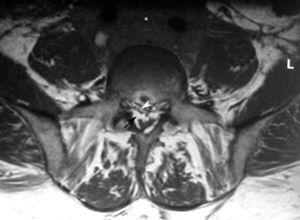

Se realizó una resonancia magnética (RM) de la columna lumbar (sin y tras contraste intravenoso) y se observaron, además de la masa retroperitoneal que comprimía la VCI, unas imágenes puntiformes y lineales hipointensas en todas las secuencias que ocupaban el espacio epidural adyacente al muro posterior de las vértebras lumbosacras, que se extendían a través de los agujeros de conjunción hacia las partes blandas perivertebrales (figs. 1-3). Esta alteración correspondía a estructuras vasculares dilatadas dependientes del plexo venoso epidural vertebral.

Fig. 3. Resonancia magnética tras contraste intravenoso: (A) sagital línea media y (B) axial. Se aprecia masa retroperitoneal (asterisco) y dilatación secundaria de las venas radiculares. Nótese la deformidad del saco tecal provocada por lipomatosis epidural (flechas).